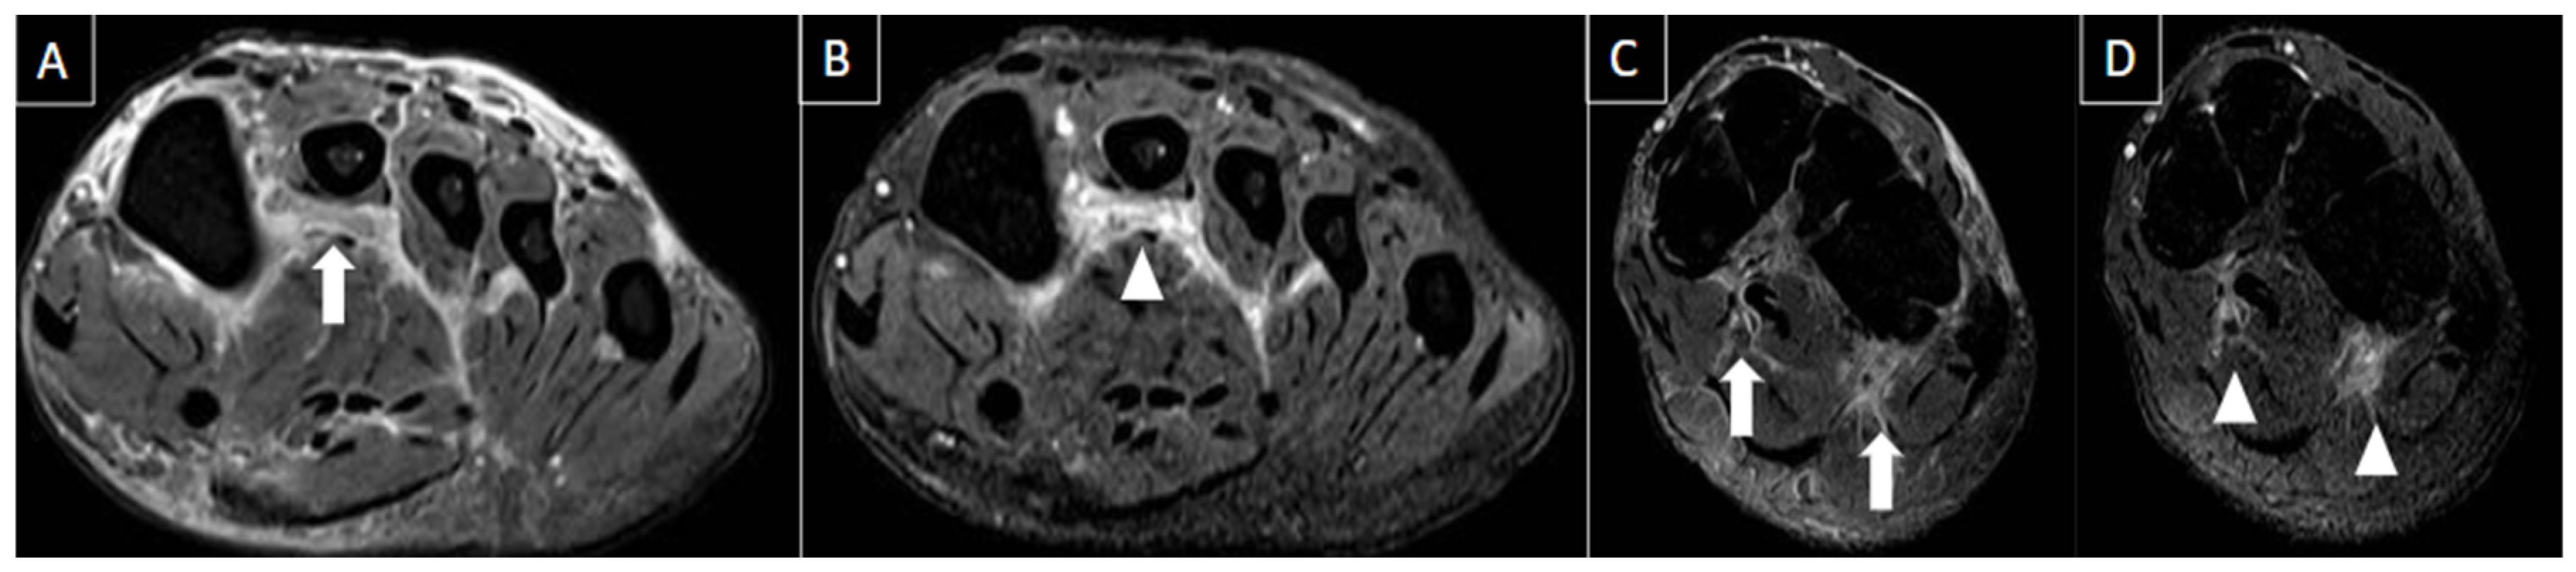

| Perivascular edema and enhancement Muscle edema Intraluminal signal change Venous enlargement Presence of collateral veins Venous filling defects (post-gadolinium injection) | Local tenderness Loss of compressibility Venous enlargement Intraluminal content Perivascular edema | Local tenderness Loss of flow Filling defects |

| Tendon pathologies | Varies according to the cause (tendinosis/ tendinopathy, tenosynovitis, and peritendinitis). | Intra and peritendinous alterations with enlargement of the tendon and various degrees of hypoechogenicity. | Enlargement and signal abnormalities in the affected tendon. High signal intensity can be seen involving the tendon and peritendinous soft tissues. |